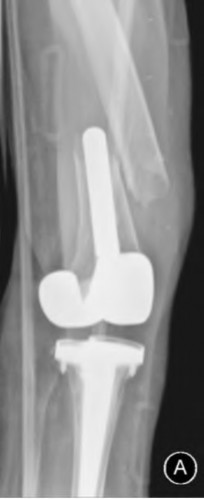

A 65-year-old woman with painful knee arthritis and the deformity seen in Figure A, is scheduled to undergo a total knee arthroplasty. All the following are risk factors for a post-operative peroneal palsy EXCEPT:

The clinical presentation is consistent with end-stage arthritis in a valgus knee. All of the factors listed are risk factors for peroneal nerve palsy EXCEPT female gender, which is not a risk factor.

Peroneal nerve palsy is a potential serious complication of TKA in patients with a pre-operative valgus knee deformity. Peroneal nerve palsy is likely caused by lengthening of the lateral aspect of the knee and subsequent traction on the peroneal nerve. It is generally recommended that patients be evaluated

carefully for symptoms postoperatively. If peroneal nerve palsy symptoms are discovered, the knee should be flexed to relax the tension that is effectively being placed on the nerve. If peri-operative nerve exploration or decompression is undertaken, the posterior border of the biceps-femoris tendon is the proper site of identification.

Idusuyi et al. published a retrospective review of 32 postoperative peroneal nerve palsies in thirty patients in which they identified possible risk factors. Prior proximal tibial osteotomy, lumbar laminectomy (thought to be a “double-crush” phenomenon), and preoperative valgus alignment of 12 degrees or more were all identified as risk factors. Other concerns included epidural anesthesia for postop pain control, preoperative flexion contractures and tourniquette time greater than 120 minutes also increased concern.

Favorito et al reviewed valgus total knee arthroplasty and reported that the most common complications of patients with a valgus deformity include: tibiofemoral instability (2% to 70%), recurrent valgus deformity (4% to 38%), postoperative motion deficits requiring manipulation (1% to 20%), wound problems (4% to 13%), patellar stress fracture or osteonecrosis (1% to 12%), patellar tracking problems (2% to 10%), and peroneal nerve palsy (3% to 4%).

Figure A demonstrates and AP radiograph of the knee showing end-stage arthritis with severe lateral compartment narrowing.